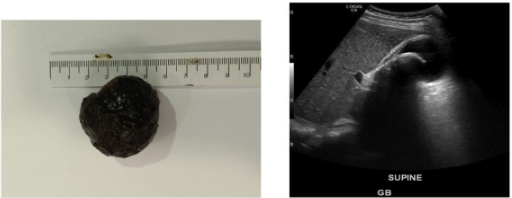

病例2术后胆囊及胆囊结石,大小约4.5*3.1*3.5cm

一名菲律宾41岁女性患者,因右上腹疼痛,呕吐三天于急诊就诊,无发热和黄疸,无慢性病病史,无手术史。查体右上腹压痛明显,墨菲征阳性。肝功能正常,白细胞计数偏高。腹部超声提示胆囊内较大结石,约4cm,胆汁淤积,胆囊壁增厚。诊断为胆囊结石伴急性胆囊炎,全麻下行腹腔镜下胆囊切除术,术中见胆囊炎症较重,结肠肝区和网膜附着于胆囊壁上,钝性分离,见胆囊壁水肿明显,Hartmann袋被胆囊结石充满,游离胆囊三角,分别夹闭胆囊动脉及胆囊管并给予离段,出标取本,见胆囊大小为4.5*3.1*3.5cm。术后患者恢复良好,两天后出院,病理提示急性胆囊炎。随访两周,无特殊不适。